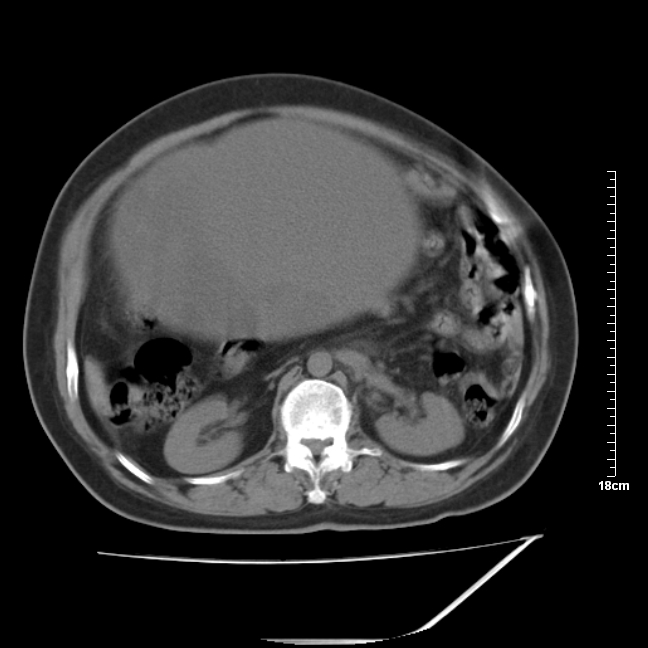

以下是引用jinning在2007-5-17 11:18:00的发言:[br]考虑右侧卵巢囊腺瘤合并少量出血可能性大